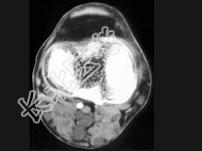

- 单项选择题男,35岁, 皮肤可见咖啡色素斑,关节疼痛, 结合图像,最可能的诊断是 ( )

A、骨肉瘤

B、骨转移瘤

C、神经纤维瘤

D、骨软骨瘤

E、纤维肉瘤